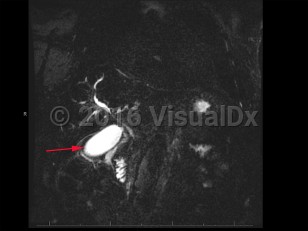

Imaging Studies image of Cholangiocarcinoma - imageId=8368519. Click to open in gallery.  caption: '<span>MCRP demonstrates peripheral and central enhancement consistent with cholangiocarcinoma.</span>'

MCRP demonstrates peripheral and central enhancement consistent with cholangiocarcinoma.